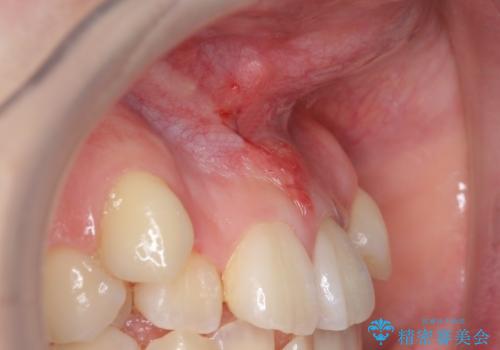

上唇小帯切除 矯正前の予防的外科処置

上唇小帯切除 矯正前の予防的処置